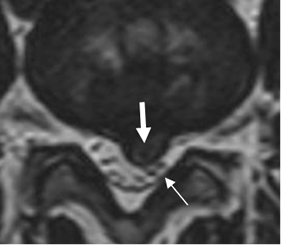

El efecto de masa y la compresión de las raíces nerviosas, no son los únicos responsables de la radiculopatía. La inflamación, factores inmunológicos y cambios vasculares, son factores que contribuyen al dolor. (20). (Fig 82 y 83).

Fig 83. Efecto de hernia.

RM axial en T2. Prominencia asimétrica (Flecha gruesa), que desplaza y comprime las raíces posteriormente. (Flecha delgada).